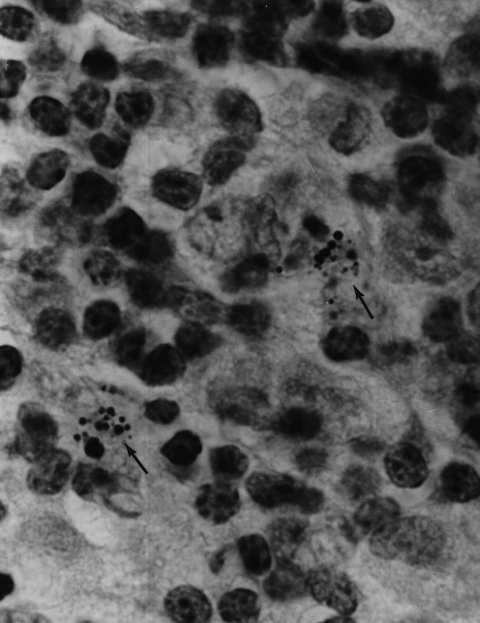

The following 9 microphotographs show various forms of the cancer microbe in vivo  in  examples of Hodgkin’s lymphoma and non-Hodgkin’s lymphoma. Additional photographs on the internet can be found by Googling: “alan cantwell” + lymphoma + images.”

Figure 8. Mycosis fungoides (T-cell lymphoma)  of the skin showing a large clump of closely-knit coccoid forms in the dermis. Alexander-Jackson’s intensified triple stain for the detection of non-acid-fast forms of mycobacteria, x1000, in oil.

Figure 9. Mycosis fungoides (T cell lymphoma) of the lymph node showing an intracellular clump of tightly-packed coccoid forms. Alexander-Jackson’s triple stain, x 1000, in oil. Compare the size and shape of the node forms to those seen in the skin in Figure 7 from the same patient.